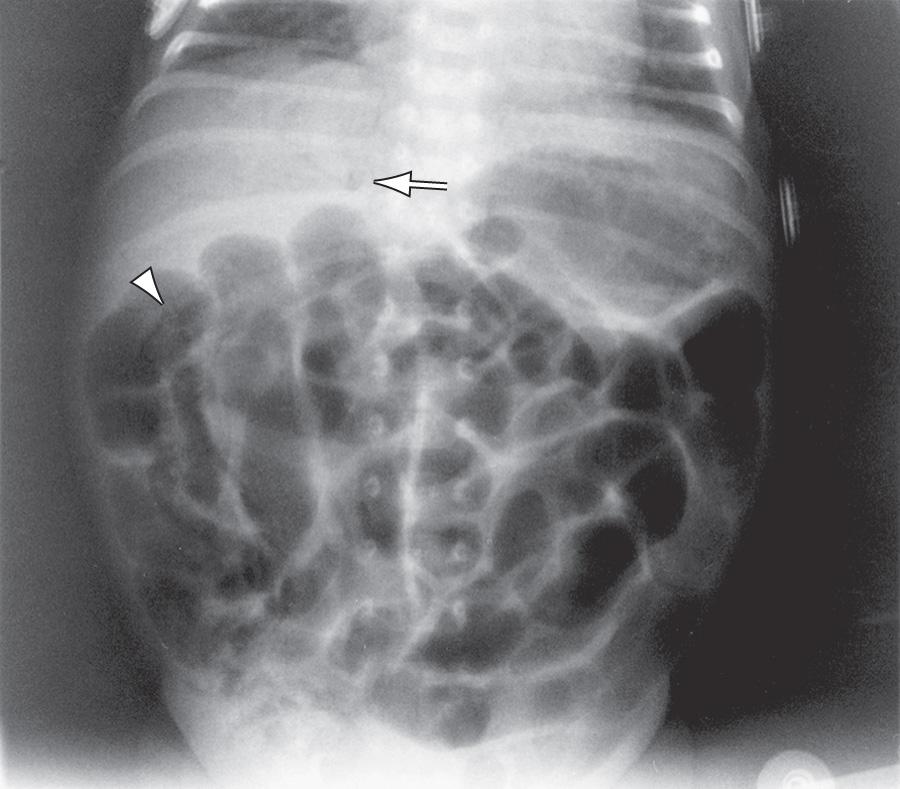

In contrast to the generally evenly distended intestinal loops above an atresia, the loops may vary in width and are not as evenly filled with gas. At points of heaviest meconium concentration, the infiltrated gas may create a bubbly, granular appearance ( Figs. 123.2 and 123.3 ).

Fig. 123.2, Meconium ileus.

Fig. 123.3, Uncomplicated meconium ileus.